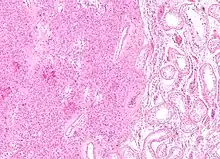

Histopathology of a Leydig cell tumor, high magnification, H&E stain, showing typical features.[1] | |

A conclusive diagnosis is made via histology, as part of a pathology report made during or after surgery. Reinke crystals are classically found in these tumours and help confirm the diagnosis, although they are seen in less than half of all Leydig cell tumours. Immunohistochemical markers of Leydig cell tumours include inhibin-alpha, calretinin, and melan-A.[6]